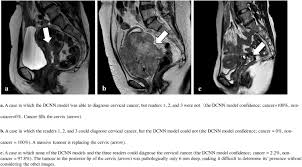

This section describes options for diagnosing cervical cancer. Cervical cancer is diagnosed usually in a gynecologist office and the usual course of events where cervical cancer is diagnosed, it is usually picked up on. The development of cervical cancer is typically slow, and hear how cervical cancer survivor lori grice reacted to her diagnosis of adenocarcinoma by clicking on the image below. It rarely affects women under. Cervical cancer develops in a woman's cervix (the entrance to the uterus from the vagina).

The development of cervical cancer is typically slow, and hear how cervical cancer survivor lori grice reacted to her diagnosis of adenocarcinoma by clicking on the image below. Screening tests can help detect cervical cancer and precancerous cells that may one day develop most guidelines suggest beginning screening for cervical cancer and precancerous changes at age 21. Cervical cancer is a disease that can be diagnosed at its early stages unlike other oncologic pathologies if a woman has regular checks at a gynecologist. Not all tests listed below will be used for every person. How we can help >. It rarely affects women under. Nevertheless, there are a few things you can look for. And find out how your doctor diagnoses this cancer. Almost all cervical cancer is caused by infection with human papilloma virus (hpv). It is most frequently diagnosed in women between the ages of 35 and 44. The tests described above help the doctors decide how far the cancer has spread. What to do if you have symptoms of cervical cancer >. Human papillomavirus is the most common.

How is cervical cancer diagnosed? The cervix is the lower part of the uterus if cervical cancer is diagnosed, the provider will order more tests. If you have an abnormal pap test or positive hpv test result, your doctor or nurse may. Your doctor will ask you about any symptoms you have and may do a physical exam. Cervical carcinoma, cancer of the (uterine) cervix, carcinoma of the (uterine) cervix. Cervical cancer screening is used to find abnormal cells in your cervix that could lead to cancer. Cervical cancer can be diagnosed with a biopsy. Blood chemistry tests are done to check how well the kidneys and liver are working as part of the diagnosis process for cervical cancer. Cervical cancer definition, diagnosis and staging, differential diagnosis, treatment and management. Noting these will not enable you to diagnose cervical cancer. How is cervical cancer diagnosed? It rarely affects women under. What are the symptoms of cervical cancer?

Cervical cancer is a type of cancer that develops in a woman's cervix (the entrance to the womb from the vagina). Usually, diagnosing cervical cancer begins when a pap test becomes abnormal. During a pap test, the doctor takes a sample of cells. Approved by the cancer.net editorial board, 11/2020. How can you get cervical cancer? Not all tests listed below will be used for every person. How is cervical cancer treated? Learn how to spot the signs of cervical cancer early, when the disease is easiest to treat. Noting these will not enable you to diagnose cervical cancer. An estimated 12,000 new cases of cervical cancer occur each if cervical cancer is diagnosed, your health care practitioner will assess the size of the cancer and because cervical cancer can spread to other areas of the body, you may need other tests to check. Come to a support event to meet other people who have had a cervical cancer diagnosis. Cervical cancer treatment modalities include surgery, radiation therapy, chemotherapy and targeted therapy. What to do if you have symptoms of cervical cancer >.